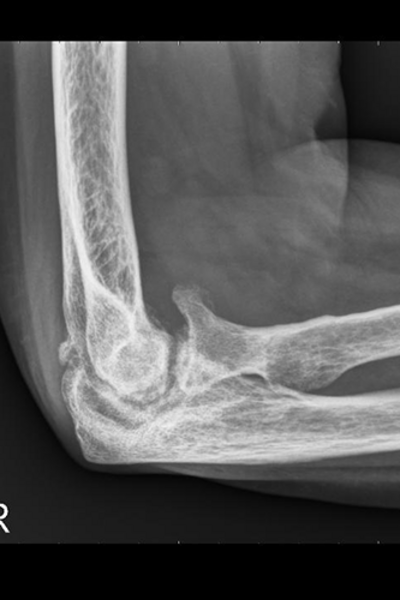

Vorher

Ellbogenröntgen seitlich

Cubitalarthrose Grad 4

Ellbogenröntgen ap